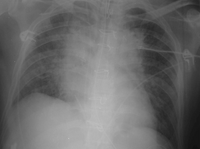

| Chronic obstructive bronchitis (COPD) exacerbation | Worsening shortness of breath + cough in known COPD.[6]

Increased sputum production[6] |

Culture of sputum in mild disease not always helpful as may give confusing results.[6]

Consider: Blood tests[6] |

Consider: Short-acting bronchodilator[6] Prevention Reduce indoor air pollution[6] Vaccinations: pneumonia vaccine, influenza vaccine, COVID-19 vaccine[6] |

Antibiotics not necessary in mild illness.[6] | |||